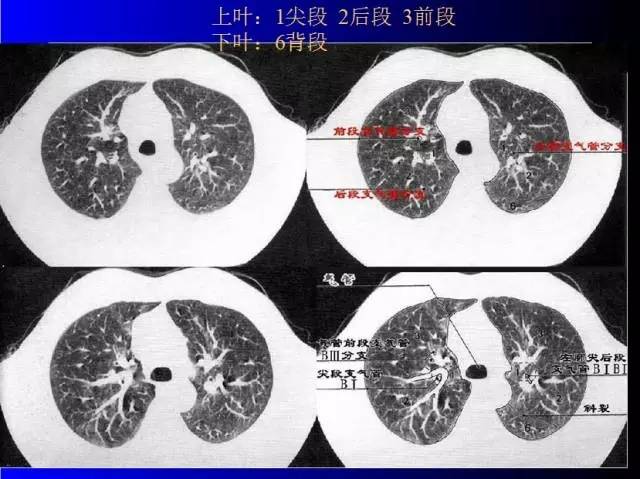

肺部基础X片及CT片解读